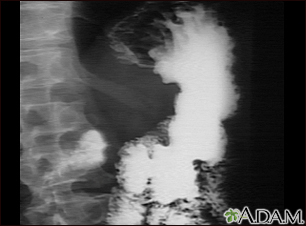

Stomach cancer, x-ray